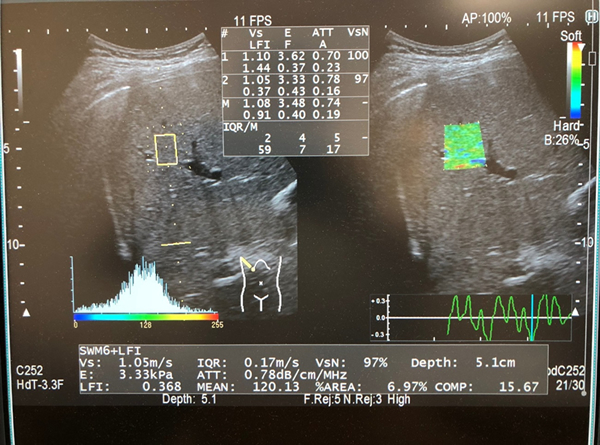

計算能力の向上で超音波診断装置が進化、脂肪を定量化して脂肪肝を早期発見日経クロステック xTECH。

超音波検査で脂肪肝を,みて,見て,診よう 4。

キヤノンメディカルシステムズ、『肝臓の脂肪量の汎用超音波画像診断装置による正確な測定法の確立の検討』に関する国内多施設臨床研究をサポート映像情報Medical。

メディカルwatch » Blog Archive » 『肝臓の脂肪量の汎用超音波画像診断 装置による正確な測定法の確立の検討』に関する国内多施設臨床研究に関して。